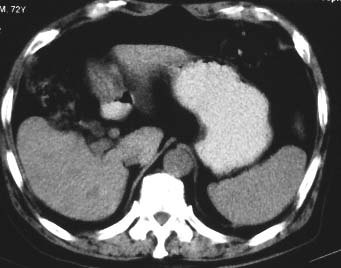

男 56 腹部不舒

典型肝硬化:1、肝各叶大小的比例失常;2、肝表面明显凹凸不整,边缘变钝;3、肝实质密度一般与正常肝无明显改变;4、肝裂增宽;5、门静脉增宽,脾静脉扩张扭曲;6、脾脏虽然不大,但不是所以肝硬化的脾脏都增大。

典型肝硬化:1、肝各叶大小的比例失常;2、肝表面明显凹凸不整,边缘变钝;3、肝实质密度一般与正常肝无明显改变,但肝右叶似可见再生结节影;4、肝裂增宽;5、门静脉增宽,脾静脉扩张扭曲;6、脾脏增大. 脾脏大小的标准有:1脾脏的左右径(大于5个肋单元) 2脾脏的宽度 3脾脏的上下径(超过肝下缘) 请参考.

典型肝硬化:1、肝各叶大小的比例失常;2、肝表面明显凹凸不整,边缘变钝;3、肝实质密度一般与正常肝无明显改变,但肝右叶似可见再生结节影;4、肝裂增宽;5、门静脉增宽,脾静脉扩张扭曲;6、脾脏增大.

典型肝硬化:1、肝各叶大小的比例失常;2、肝表面明显凹凸不整,边缘变钝;3、肝实质密度一般与正常肝无明显改变,但肉眼观察与脾胀密度低或等密度;4、肝裂增宽;5、门静脉增宽,脾静脉扩张扭曲;6、脾脏增大.

典型肝硬化:1、肝各叶大小的比例失常;2、肝表面明显凹凸不整,边缘变钝;3、肝实质密度一般与正常肝无明显改变,4、肝裂增宽;5、门静脉增宽,脾静脉扩张扭曲;6、脾脏增大.